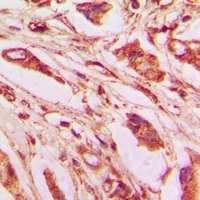

IHC (Immunohiostchemistry)

(Immunohistochemical analysis of IL-9 staining in human lung formalin fixed paraffin embedded tissue section. The section was pre-treated using heat mediated antigen retrieval with sodium citrate buffer (pH 6.0). The section was then incubated with the antibody at room temperature and detected using an HRP conjugated compact polymer system. DAB was used as the chromogen. The section was then counterstained with haematoxylin and mounted with DPX.)